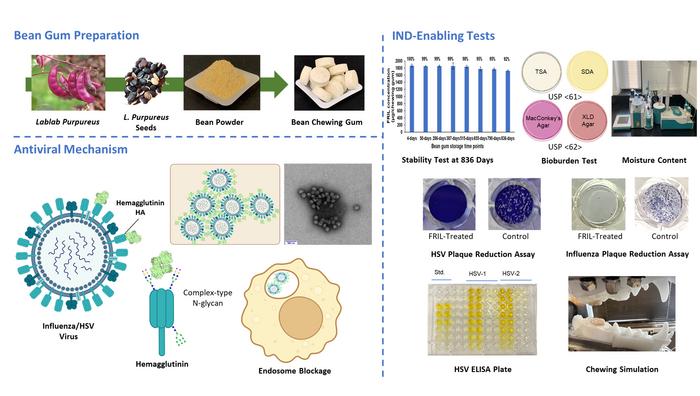

Pennsylvania Üniversitesi araştırmacıları, grip ve uçuk virüsü gibi yaygın hastalıklarla mücadelede çığır açacak bir buluşa imza attı. Lablab fasulyesinden üretilen özel bir sakız, ağızda çiğnendiğinde virüsleri tuzağa düşürerek bulaş riskini yüzde 95 oranında azaltıyor. İşte herkesin merakla beklediği bu antiviral savunmanın detayları…

Nasıl çalışıyor? Doğal fasulye proteini virüsleri etkisiz hale getiriyor!

Lablab fasulyesinde doğal olarak bulunan FRIL proteini, grip (H1N1 ve H3N2) ile herpes simplex (HSV-1 ve HSV-2) virüslerini adeta bir mıknatıs gibi çekiyor. Çiğneme sırasında tükürükle karışan bu proteinler, virüsleri yüzeye bağlayarak çoğalmalarını ve bulaşmalarını engelliyor. Testlerde sadece 40 miligram sakızın 2 gramlık tablet formu bile etkili oldu.

Klinik testler başarılı: İnsan deneyleri için hazır!

COVID-19’da yüzde 95 başarı gösteren benzer sakız formülünün ardından, bu yeni versiyon FDA standartlarına uygun şekilde üretildi. Araştırma ekibi, Günde 3-4 kez çiğnenmesi, özellikle toplu taşıma veya okul gibi kalabalık ortamlarda virüs zincirini kırabilir açıklamasını yaptı. Sakızın insanlar üzerindeki etkisi önümüzdeki aylarda test edilecek.

Kuş gribine karşı da umut oldu: Tavuk yemlerine karıştırılacak!

54 milyon kanatlıyı etkileyen H5N1 virüsüne karşı da kullanılacak olan bu teknoloji, şimdi de kümes hayvanlarını korumak için deneniyor. Lablab fasulyesi tozuyla zenginleştirilen yemlerin, hem hayvanları hem de insanları kuş gribine karşı koruyabileceği düşünülüyor. Daniell, Doğal bir çözümle küresel salgınları önlemeyi hedefliyoruz diyor.